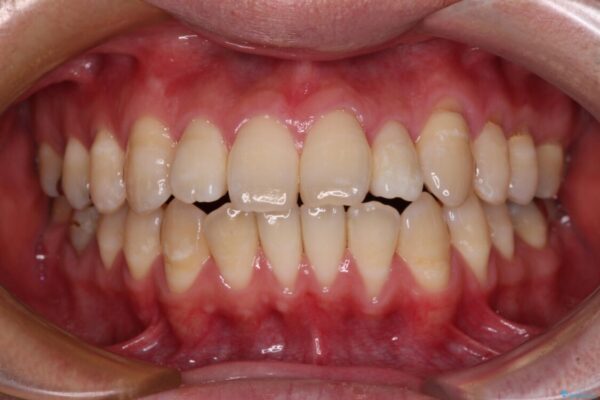

治療前

• 口元の突出感を改善!目立ちにくいワイヤー矯正で自信を持てる自然な横顔に 治療前画像

「横から見ると唇が前に出て見えるのが気になる…」 「マスクを外すのが恥ずかしい…」 そんな口元の突出感に悩まれてご来院された患者様。

精密検査の結果、上下左右の小臼歯4本を抜歯し、そのスペースに前歯を後方へ移動させる矯正治療をご提案しました。